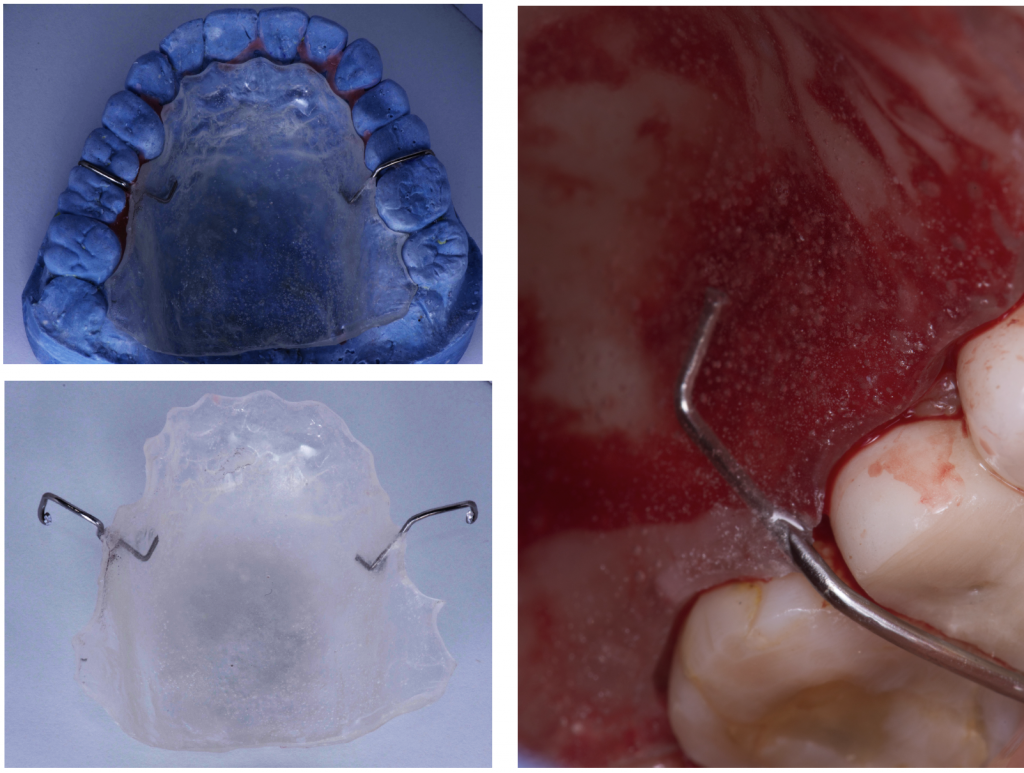

7. Confecciona una placa protectora para el paladar.

Es aconsejable tener una placa protectora, quizá no controles mucho la profundidad de tu invasión en el paladar al inicio y estabilizar con puntos de sutura en cruz las esponjas de colágeno para controlar el sangrado sea muy difícil, por ello, puedes apoyarte utilizando una placa protectora en tus primeros injertos con el objetivo de ganar tiempo quirúrgico y evitar complicaciones postoperatorias.